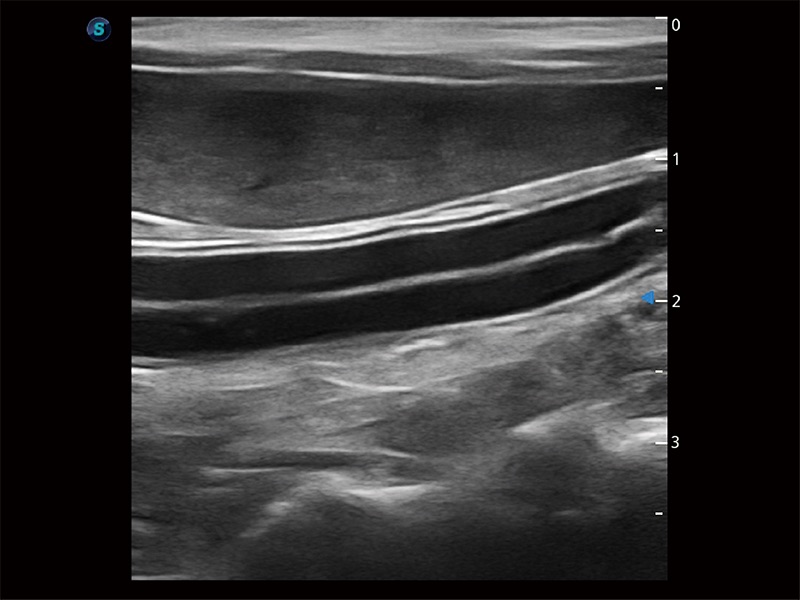

为精细结构及组织边缘提供高清晰度的图像和更大的成像视野。帮助减轻医生的用眼疲劳,快速精准获得测量的数据。